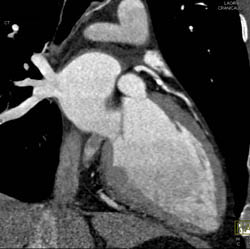

Plaque in LAD